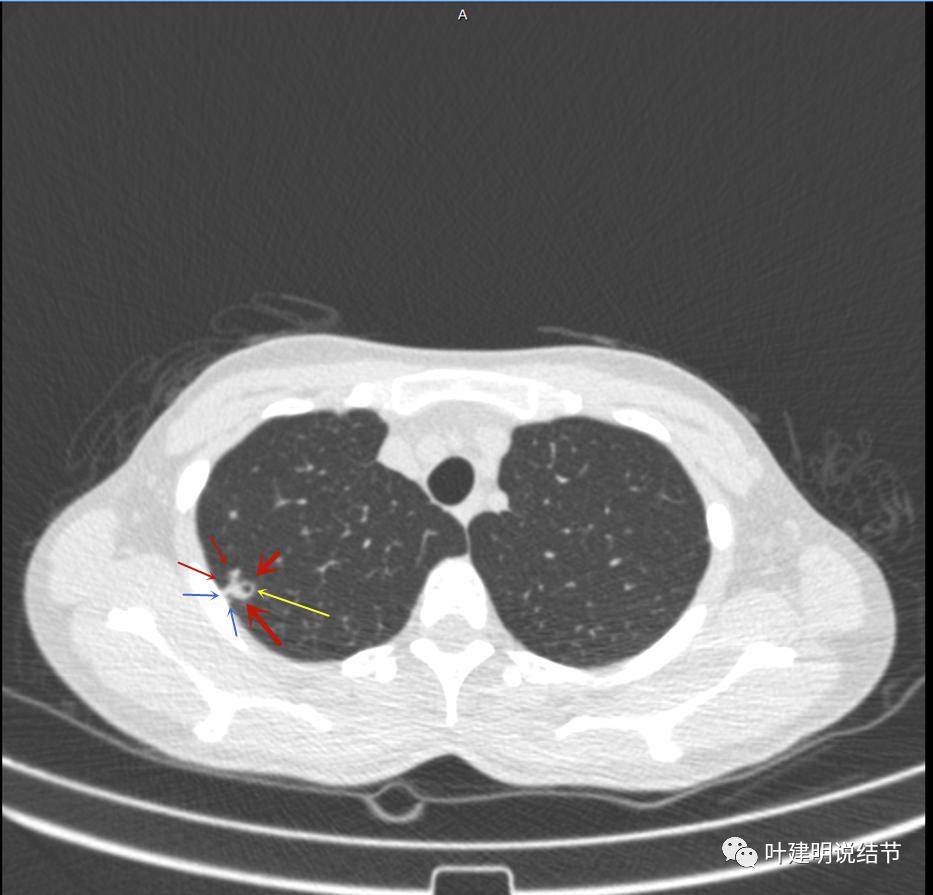

主病灶出现,粉色箭头示病灶密度较高,边上有磨玻璃影,甚淡(砖色箭头)

病灶有空洞(黄色箭头),主病灶边上见条索状高密度影(细红色箭头),邻近胸膜有粘连(蓝色箭头)